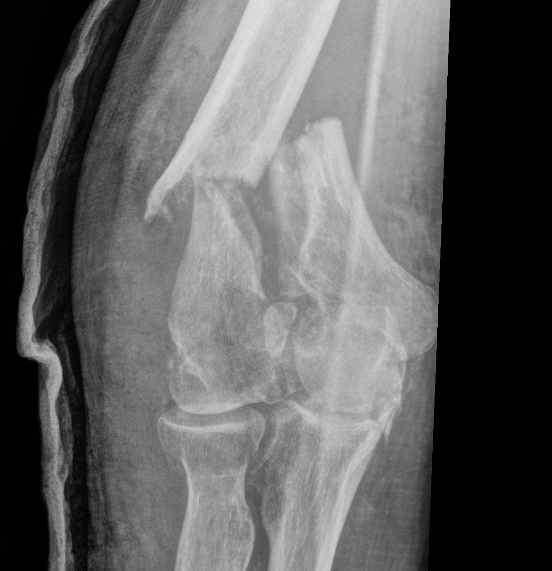

OTA / AO Classification

Type A: Extra-articular fracture

Type B: Partial articular fractures

Lateral condyle Medial condyle

Type C: Complete articular fractures

CT scan